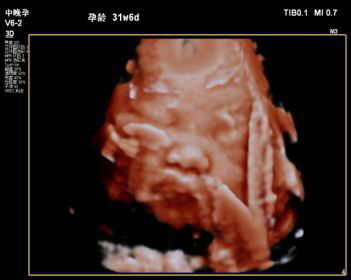

2019年我科室特引进飞利浦EPIQ5全身高档彩色多普勒超声,配备有心脏、腹部、浅表、腔内及三维容积等5把探头。其专有的purewave纯净波单晶技术,可提高在难以成像的患者身体中的穿透力,使成像更快捷、更清晰;飞利浦EPIQ5在孕期检查中也独具优势,通过图像的切割、旋转及高平面图像的分析,能直观、立体显示胎儿在母体子宫内的立体形态、表面特征、空间位置关系,尤其胎儿面部的三维成像,清晰、直观,准爸爸、准妈妈可以通过屏幕亲眼目睹胎儿的眼睛、嘴巴、鼻子和脸颊,甚至可以看到宝宝在妈妈肚子里运动、呼吸、吞咽、打哈欠、伸舌头等生理活动,非常直观。

每个孕妈妈都希望生个健康的宝宝,因此一定不要忘记这项重要的超声检查哦,不然错过时间可没有办法弥补了。我科室现已正式开展三维彩超,看这些可爱的宝宝!